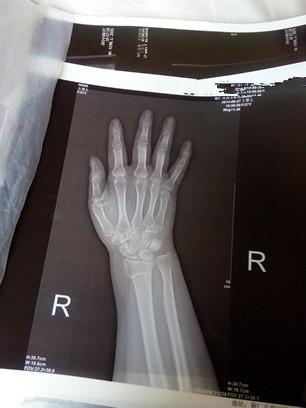

右手手腕骨裂图片

右手手腕骨裂图片,手腕骨折的真实图片

手腕骨折的真实图片

骨裂右手

骨折和骨裂的图片

骨裂的片子图片

骨裂图片

轻微骨裂图片

右手图片